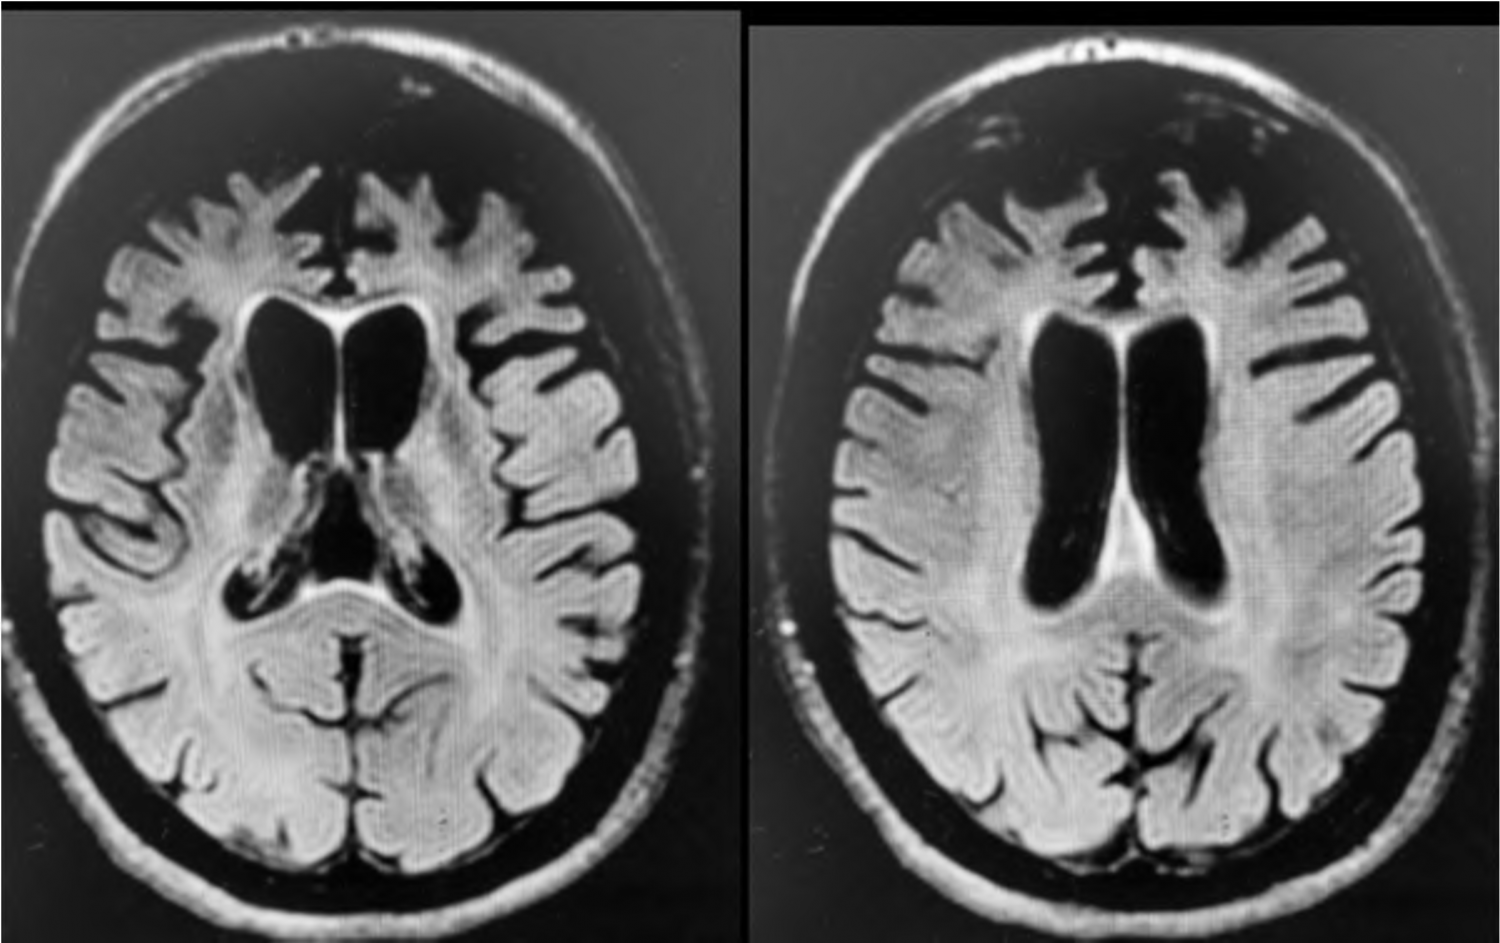

F.E.A, 64 anos, casada, superior completo, professora do ensino fundamental. Segundo os familiares, até 5 anos atrás a paciente tinha funcionalidade preservada, bom rendimento no trabalho, frequentava a igreja e atividades sociais. Nesses 5 anos começou a ficar mais retraída, reduziu contato social e permanecia mais em casa. Inicialmente pensaram que essas alterações estavam relacionadas à aposentadoria, mas com o passar do tempo começou a recusar ver filhos e netos, além de apresentar comportamento mais desinibido, sem prejuízo da necessidade de sono ou aceleração psíquica. Na avaliação clínica, verificou-se prejuízo visuoespacial e de função executiva significativos, associados a comprometimento da cognição social e pensamento lógico. Memória relativamente preservada. Funcionalidade prejudicada, com declínio das atividades instrumentais de vida diária. Ao exame físico, apresentava regular estado geral, algo descuidada, sinais vitais dentro dos parâmetros de normalidade. O exame neurológico apresentou grasping positivo, sem outras alterações. Exames gerais, EEG e líquor dentro dos parâmetros de normalidade. O exame de ressonância do crânio revelou a seguinte imagem: